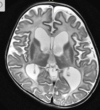

A

Cisto epidermóide

Hipersinal na difusão

Sinal heterogêneo no FLAIR

Extra-axial